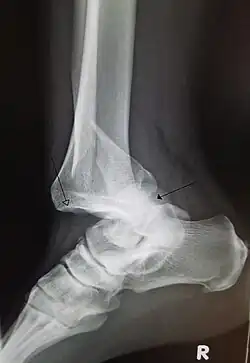

A traumatic dislocation of the tibiotarsal joint of the ankle with distal fibular fracture. Open arrow marks the tibia and the closed arrow marks the talus. | |